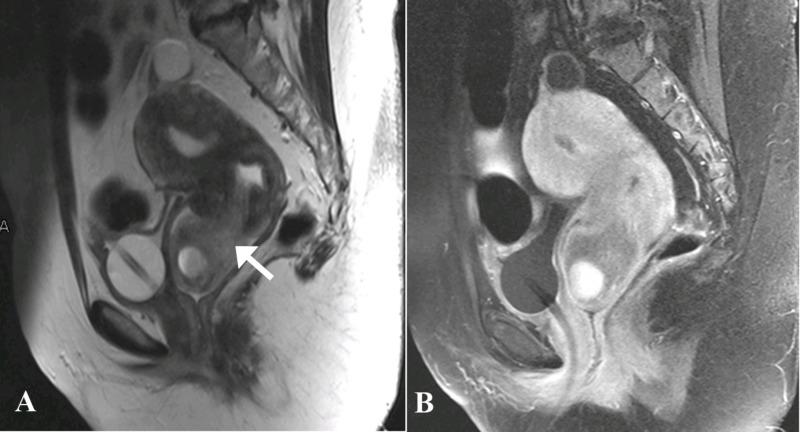

Polypoid adenomyoma is a rare uterine endometrial polypoid tumor of mixed epithelial and mesenchymal origin. Although the clinical and pathologic features of polypoid adenomyomas have been described extensively, imaging findings for these tumors have not been frequently reported in the literature. On imaging, their features may be confused with prolapsed leiomyomas or malignancy. Hemorrhagic cystic spaces in a prolapsed uterine tumor within the vagina should raise consideration of a diagnosis of polypoid adenomyoma. Such blood-containing cystic spaces would be unusual findings in leiomyomas and malignancy. Diagnosing polypoid adenomyoma is vital because it can potentially be managed by hysteroscopic resection, unlike an ordinary form of adenomyosis.

息肉样腺肌瘤是一种罕见的起源于上皮和间充质混合的子宫子宫内膜息肉样肿瘤。尽管息肉样腺肌瘤的临床和病理特征已被广泛描述,但这些肿瘤的影像学表现尚未在文献中频繁报道。在影像学上,它们的特征可能与脱垂的平滑肌瘤或恶性肿瘤相混淆。阴道内脱垂的子宫肿瘤中出现出血性囊性间隙应考虑息肉样腺肌瘤的诊断。这种含血的囊性间隙在平滑肌瘤和恶性肿瘤中是不常见的表现。诊断息肉样腺肌瘤至关重要,因为与普通形式的子宫腺肌病不同,它有可能通过宫腔镜切除术进行治疗。